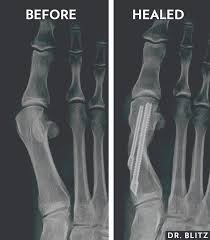

Mis Minimally Invasive Surgery Bunion Shaving Podiatrist Dr Jairo Cruz Bunion Pain Youtube from i.ytimg.com Bunion surgery for minor bunion deformities can be attempted utilizing a minimally invasive bunion approach by making a small incision to either shave down the prominent bone and/or break the bone to shift it into its correct position, and then fixate the bone with screws through another small incision. Minimally invasive surgery involves using advanced, specially designed instruments to perform sophisticated surgery through small incisions in the body or a natural orifice. Bunions can be painful and unsightly. Minimally invasive bunion surgery differs from traditional bunion surgery, and what we do at northwest surgery center is more special than anywhere else! Our minibunion procedure versus traditional minimally invasive bunion surgery. Center for minimally invasive and robotic surgery. So, many people put off fixing their bunion until they. Minimally invasive surgery • return to work in three days • visible scars heal in 8 weeks!

By avoiding large incisions, less soft tissue, such. Bunion surgery may be recommended when less invasive treatment options aren't successful. Then she had minimally invasive bunion surgery at duke and walked out just hours later. In minimally invasive surgery, doctors use a variety of techniques to operate with less damage to the body than with open surgery. Center for minimally invasive and robotic surgery. Podiatrist in woodland hills, california. Minimally invasive techniques can easily treat bunions but it can be done only for mild to moderately painful bunions. You'll usually recover more quickly, spend less time in the hospital, and feel more comfortable while you heal. Bunion surgery for minor bunion deformities can be attempted utilizing a minimally invasive bunion approach by making a small incision to either shave down the prominent bone and/or break the bone to shift it into its correct position, and then fixate the bone with screws through another small incision. By the time it becomes severe as minimally invasive techniques are developing rapidly in all areas of clinical care, minimally invasive bunion surgery is emerging as a popular. Patients say they've heard that bunion surgery is one of the most painful surgeries. Her sister had had the procedure years earlier and been off her feet for four weeks afterwards. Bunion surgery has often been known as a very painful procedure with a long recovery period.

Bunions may be corrected with conservative treatments or bunion surgery. Bunion surgery has often been known as a very painful procedure with a long recovery period. It is important that a highly experienced specialist foot. Our minibunion procedure versus traditional minimally invasive bunion surgery. Receive quick, safe and effective bunion treatment. K) on tv shows like 'the doctors'. Minimally invasive bunion surgery is performed using a burr, instead of a saw, to cut the bone. Neal blitz is a cosmetic or aesthetic approach to bunion surgery where is anesthesia provided during a bunionplasty®? You may have seen dr. Solomon, the top bunionectomy doctor, and bunion surgeon. A bunionplasty® (plastic surgery for bunions), created by bunion king™ dr. Welcome to downtown nyc foot care! By avoiding large incisions, less soft tissue, such.